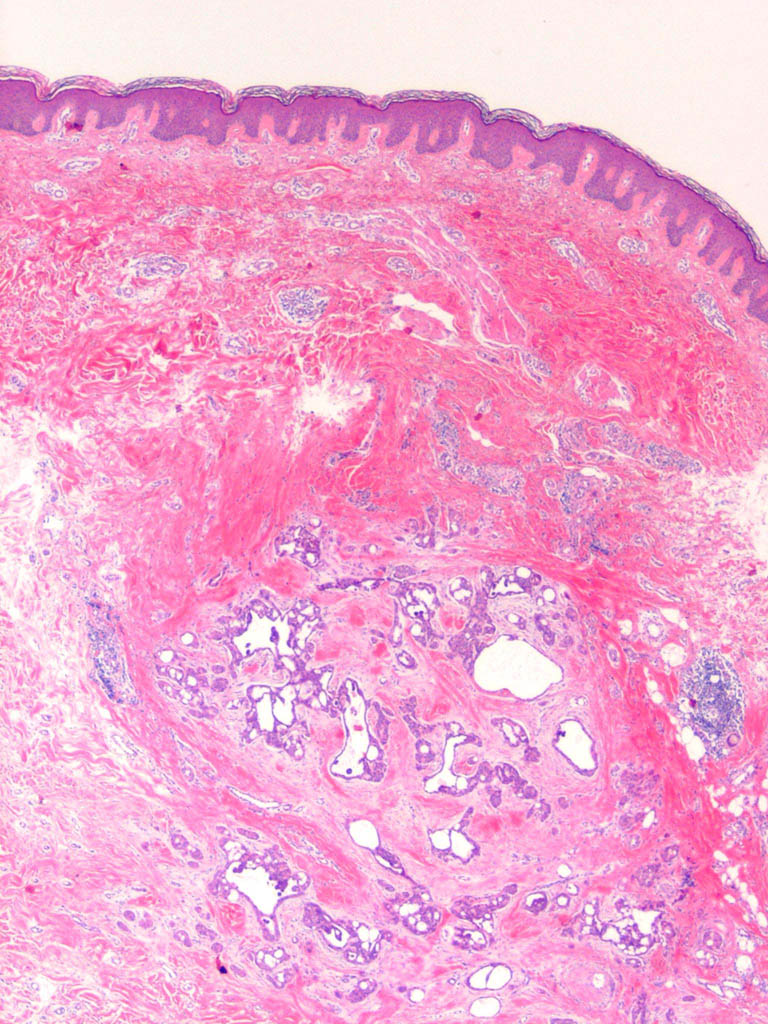

Papillary eccrine adenoma = الغدوم الناتح الحطاطي